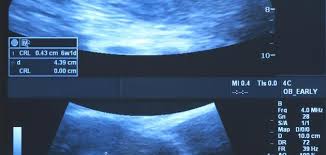

شكل الجنين في الشهر الاول بالسونار و سبب صغر كيس الحمل مجلة أبدعي